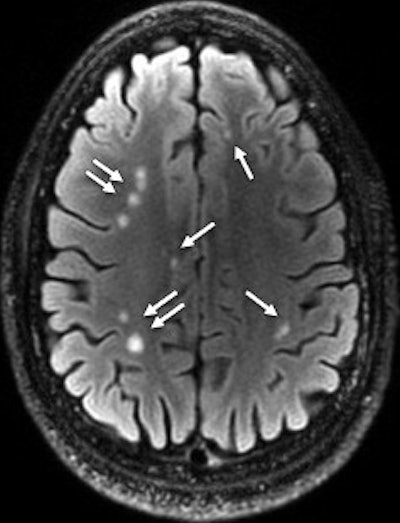

A 28-year-old man with blast-related TBI had multiple white-matter T2-weighted hyperintensities (arrows). Axial T2 FLAIR MRI discovered a total of 76 lesions on all sections. Image courtesy of Radiology.

One or more white-matter T2-weighted hyperintensities were seen in 432 subjects (52%) with TBI, compared with 16 (38%) of the 42 healthy volunteers (p = 0.057), a difference that was not statistically significant.